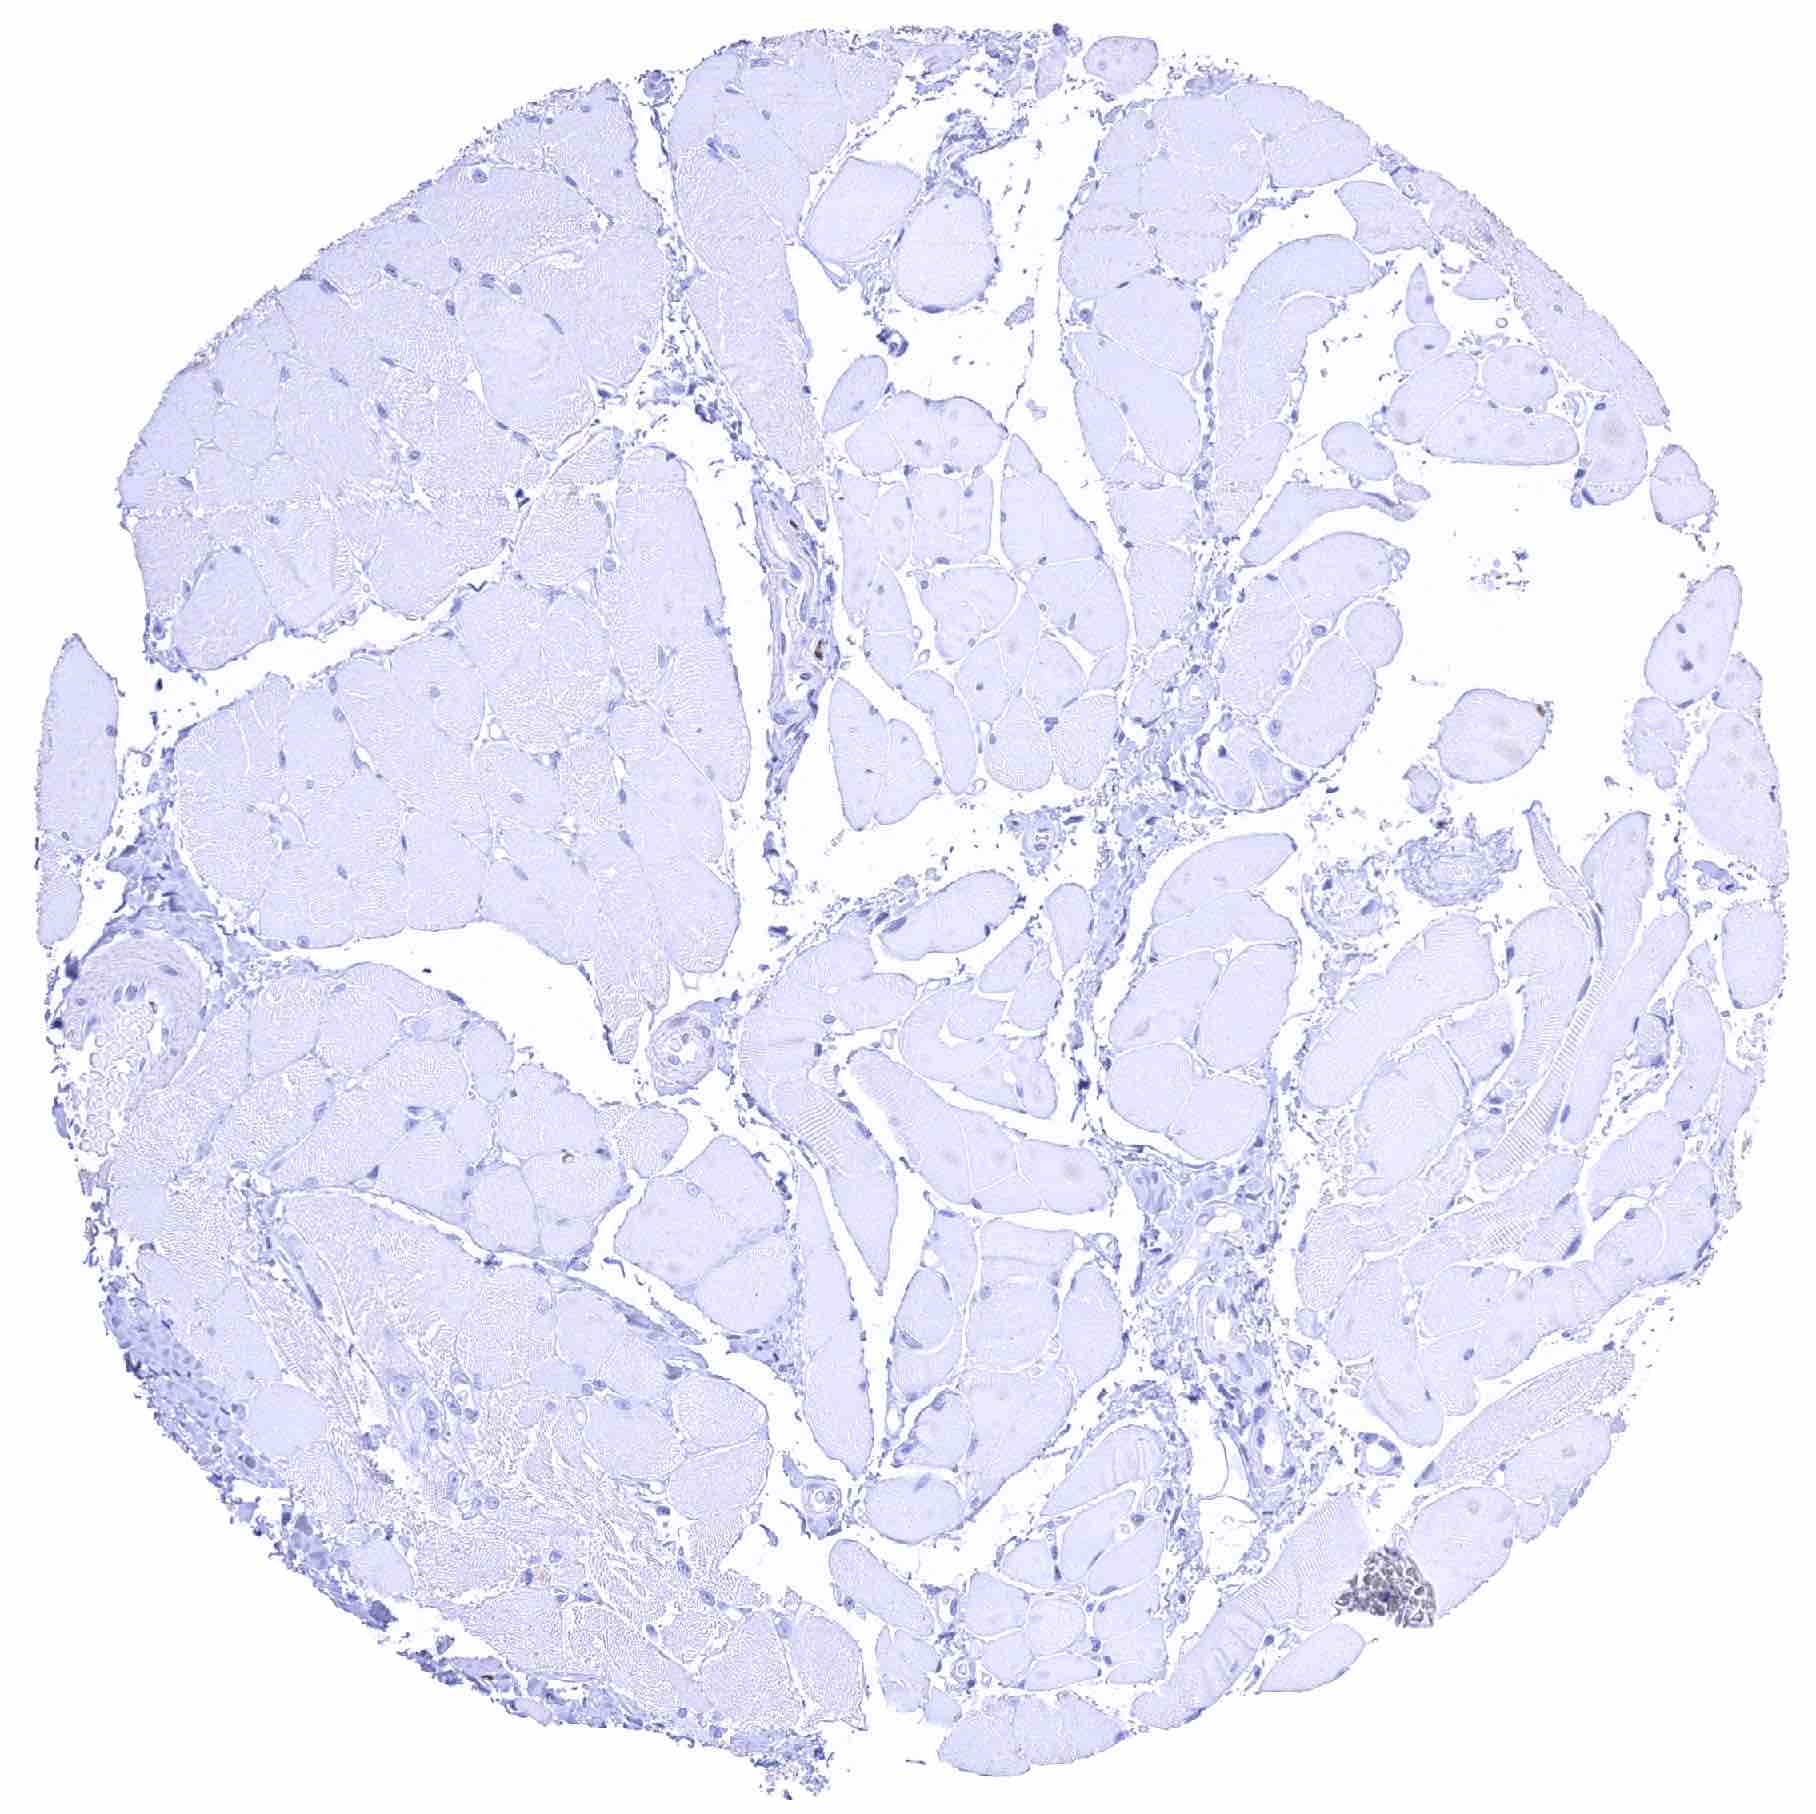

Skeletal muscle